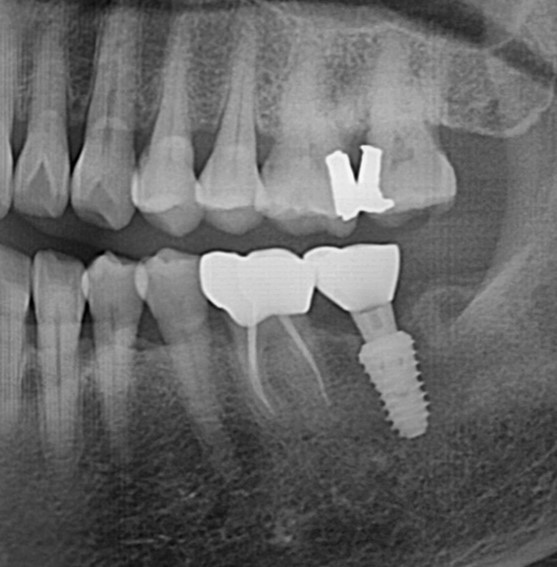

구치부 임플란트 식립사례

전후사진